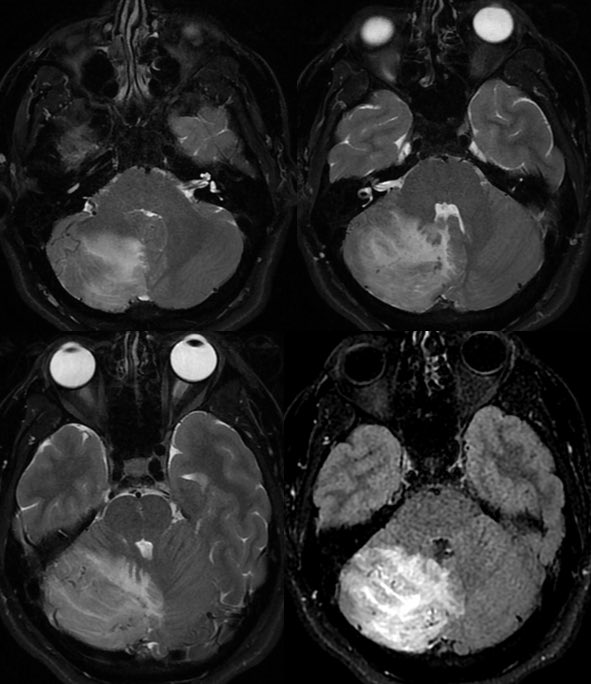

▶️DWI: No diffusion restriction

▶️SWI: patchy areas of hemorrhage and engorged vessels